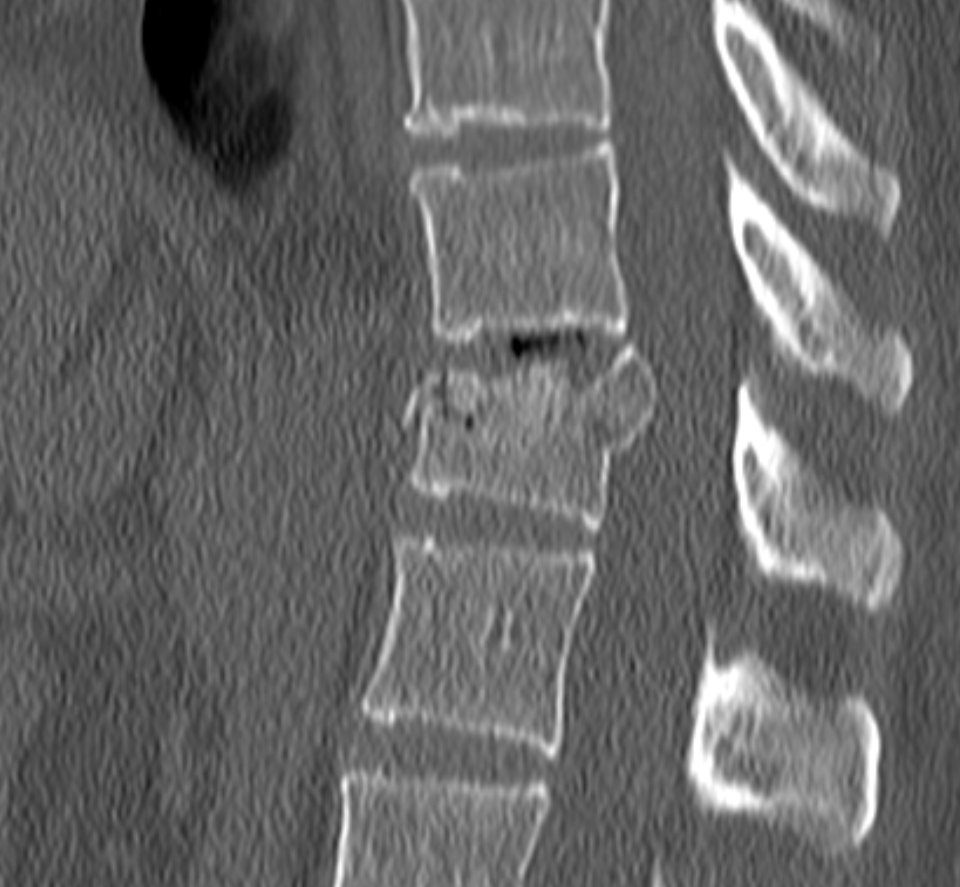

Male. Age 82.

Slipped on a wet floor. Subsequently complaining of neck pain. On examination: some tenderness in the upper cervicle spine.

Normal or abnormal appearances?

RADIOGRAPHS